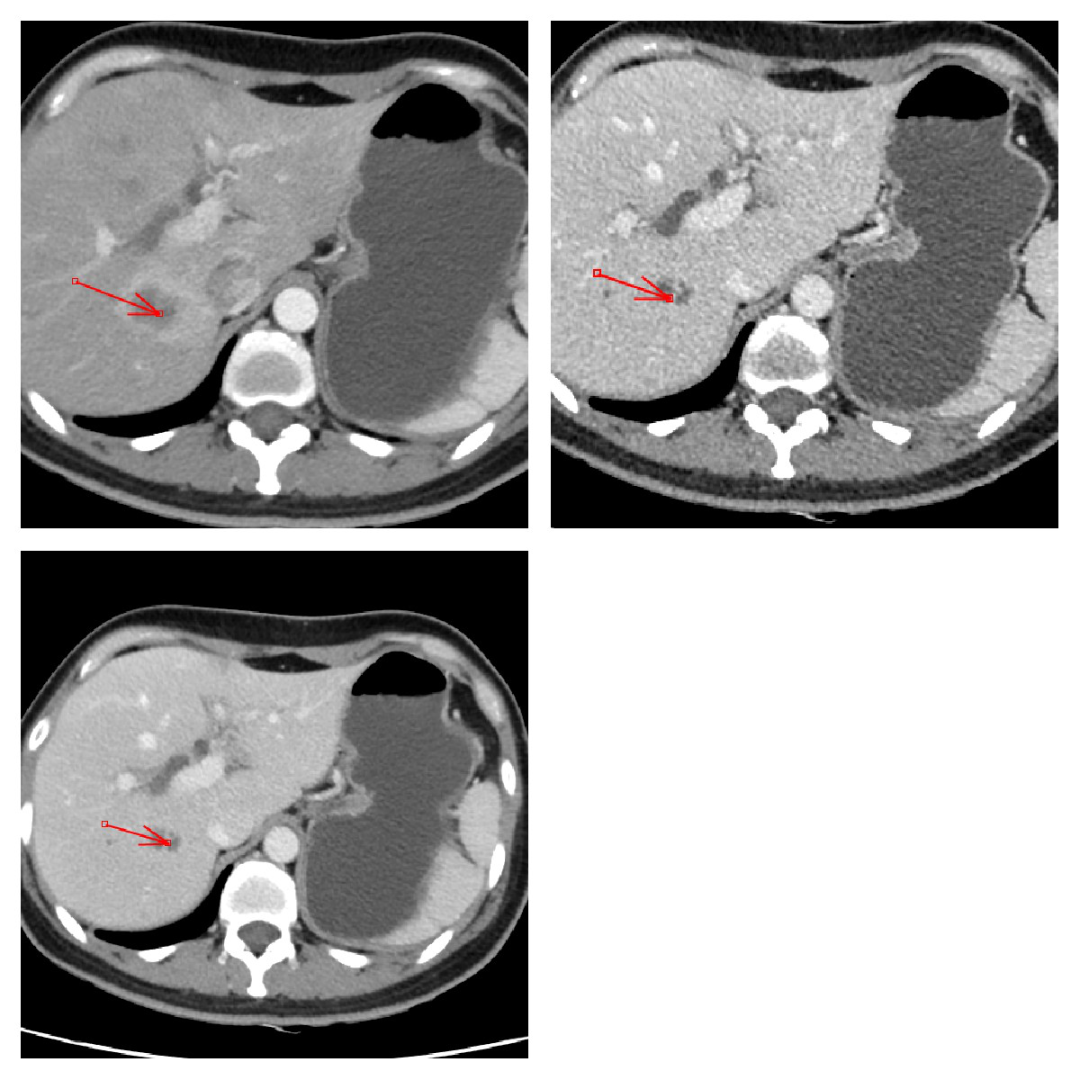

脉管癌栓:肝细胞肝癌容易发生脉管癌栓,ct 平扫显示为沿门脉走形区增宽;动脉期可见门脉走形区内不规则强化影;静脉期及延迟期强化减低。